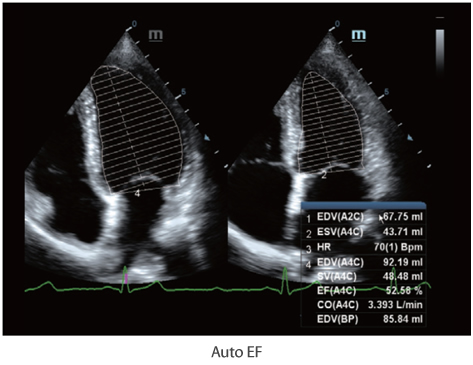

Auto EF

Auto EF es una manera inteligente de analizar eco-clips 2D para automáticamente reconocer los cuadros diastólicos y sistólicos y producir una serie de medidas, con las que evaluar rápidamente el rendimiento del ventrículo izquierdo para una mayor productividad del usuario, incluyendo EDV/ESV/EF.